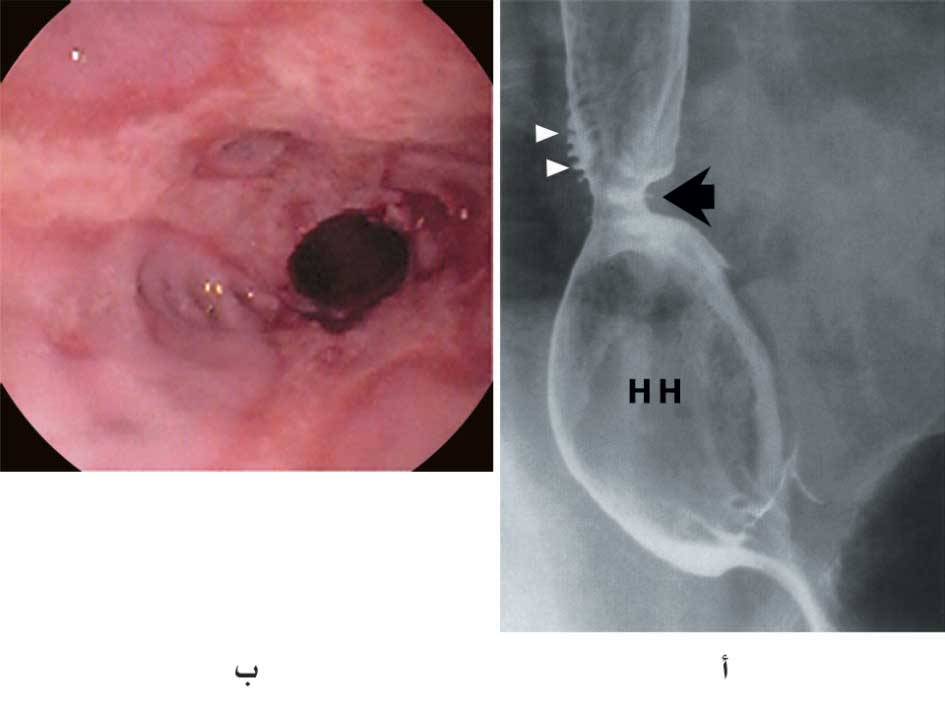

| الشكل (1) أ- تضيق المريء الناجم عن التهاب المري الهضمي كما يبدو في الصورة الشعاعية (السهم الأسود). تكشف الصورة أيضاً وجود فتق حجابي كبير شائع المصادفة في تضيقات المريء الهضمية (HH) إضافة إلى وجود عدة رتوج كاذبة أسفل المريء (الأسهم البيضاء) ب- تضيق المريء كما يبدو بالتنظير الداخلي ويكشف أيضاً التهاب مريء هضمي يشمل كامل محيط المريء (الدرجة IV من تصنيف لوس أنجلوس) |